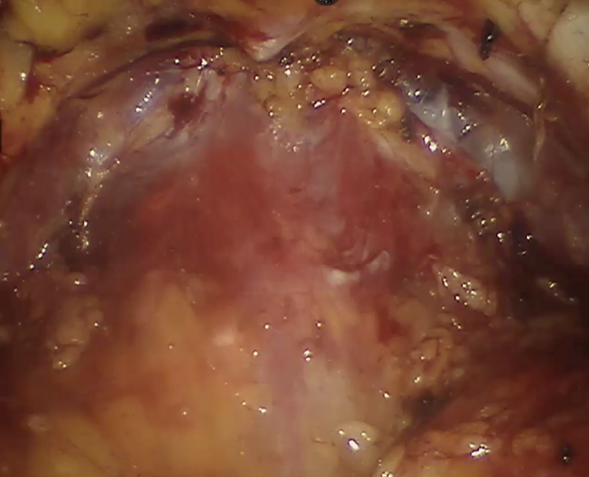

El procedimiento comienza con la exposición del espacio de Retzius, movilizando la vejiga incidiendo el pliegue de peritoneo parietal en el domo y el ligamento umbilical en línea media. Una vez que la vejiga es liberada y desplazada caudalmente, la grasa periprostática y el ligamento puboprostático son separados de la fascia endopélvica. En este paso se debe tener cuidado con el control del complejo venoso dorsal, el cual es ligado con sutura V-loc 3-0 y resecado para tener mejor exposición de la cápsula prostática. (Figura 1) Una vez formado un espacio retropúbico amplio y expuesta la unión vesicoprostática, se procede a incidir en línea media.

Exposición del espacio de Retzius, observando la cara anterior de la cápsula prostática. Se realizó la ligadura y resección del complejo venoso dorsal. Se observan ligamentos puboprostáticos lateralmente.

Figura 1 Exposición del espacio de Retzius